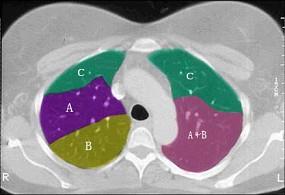

问题 结合肺段模式肺动脉干与右肺动脉层面肺动脉干与右肺动脉层面(见图), 心室层面(见图), 主动脉弓层面(见图), 左右心房层面(见图),选出左肺上叶的组成 ( )

选项 A、A+B+C+D+E B、A+B+C+D+E+F C、A+B+C D、A+B+C+D E、A+B

答案 A